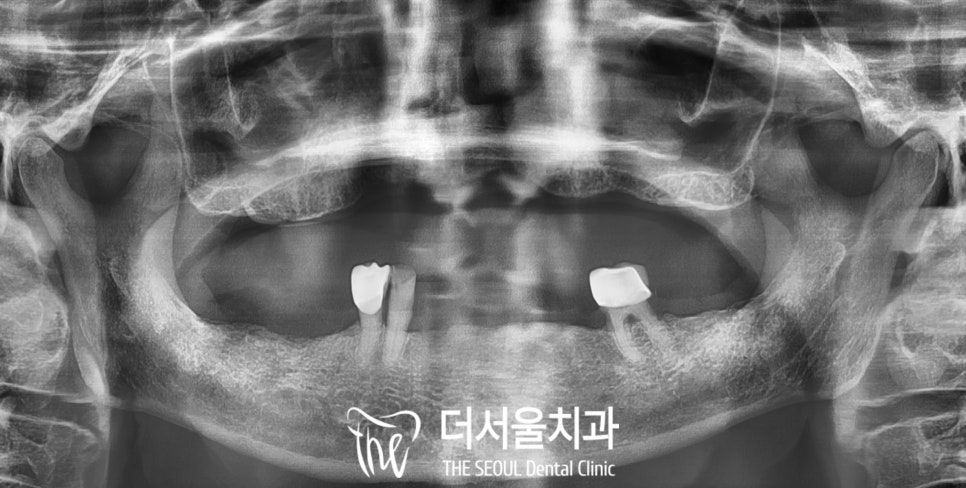

구강을 살펴보면

정말로 상악은 치아가 하나도 없는

무치악상태이셨고,

하악은 세개정도의 이가 남아있어

부분틀니를 걸어서 사용중이시나

동요도에 따라 발치를 해야될 수도 있겠습니다.

또한 오랜 덴처 사용으로

치조골이 많이 얇아져 있었으며

상처가 생긴 곳도 있네요.

2. 진단

분당 치과 에서

파노라마 엑스레이를 찍어

이제는 틀니 대신

임플란트를 할 수 없을까

자세히 살펴보았습니다.

상악은 뼈의 높이가 낮아져있긴 하나

디지털 풀아치의 도움을 받으면

최소 개수로

안정적으로 식립이 가능해 보였으며

하악도 왼쪽 아래 어금니를 제외하고는

자연치를 보존하면서

부족한 부분은 식립을 하는 방향으로

계획을 세웠습니다.